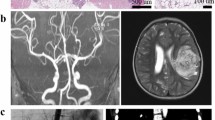

A case of polyarteritis is reported in an 18-year old woman, occurring 2 years after an allogeneic bone marrow transplant. The clinical manifestations were similar to those of polyarteritis nodosa (PAN) with a wide range of organs involved including life-threatening cardiac and mesenteric problems requiring plasmapheresis and intravenous immunoglobulin (IgIV).

Ysebaert, L., Deconinck, E., Larosa, F. et al. Polyvisceral arteritis in chronic graft-versus-host disease: antiphospholipid-negative thrombotic syndrome mimicking polyarteritis nodosa. Bone Marrow Transplant 29, 873–874 (2002). https://doi.org/10.1038/sj.bmt.1703560